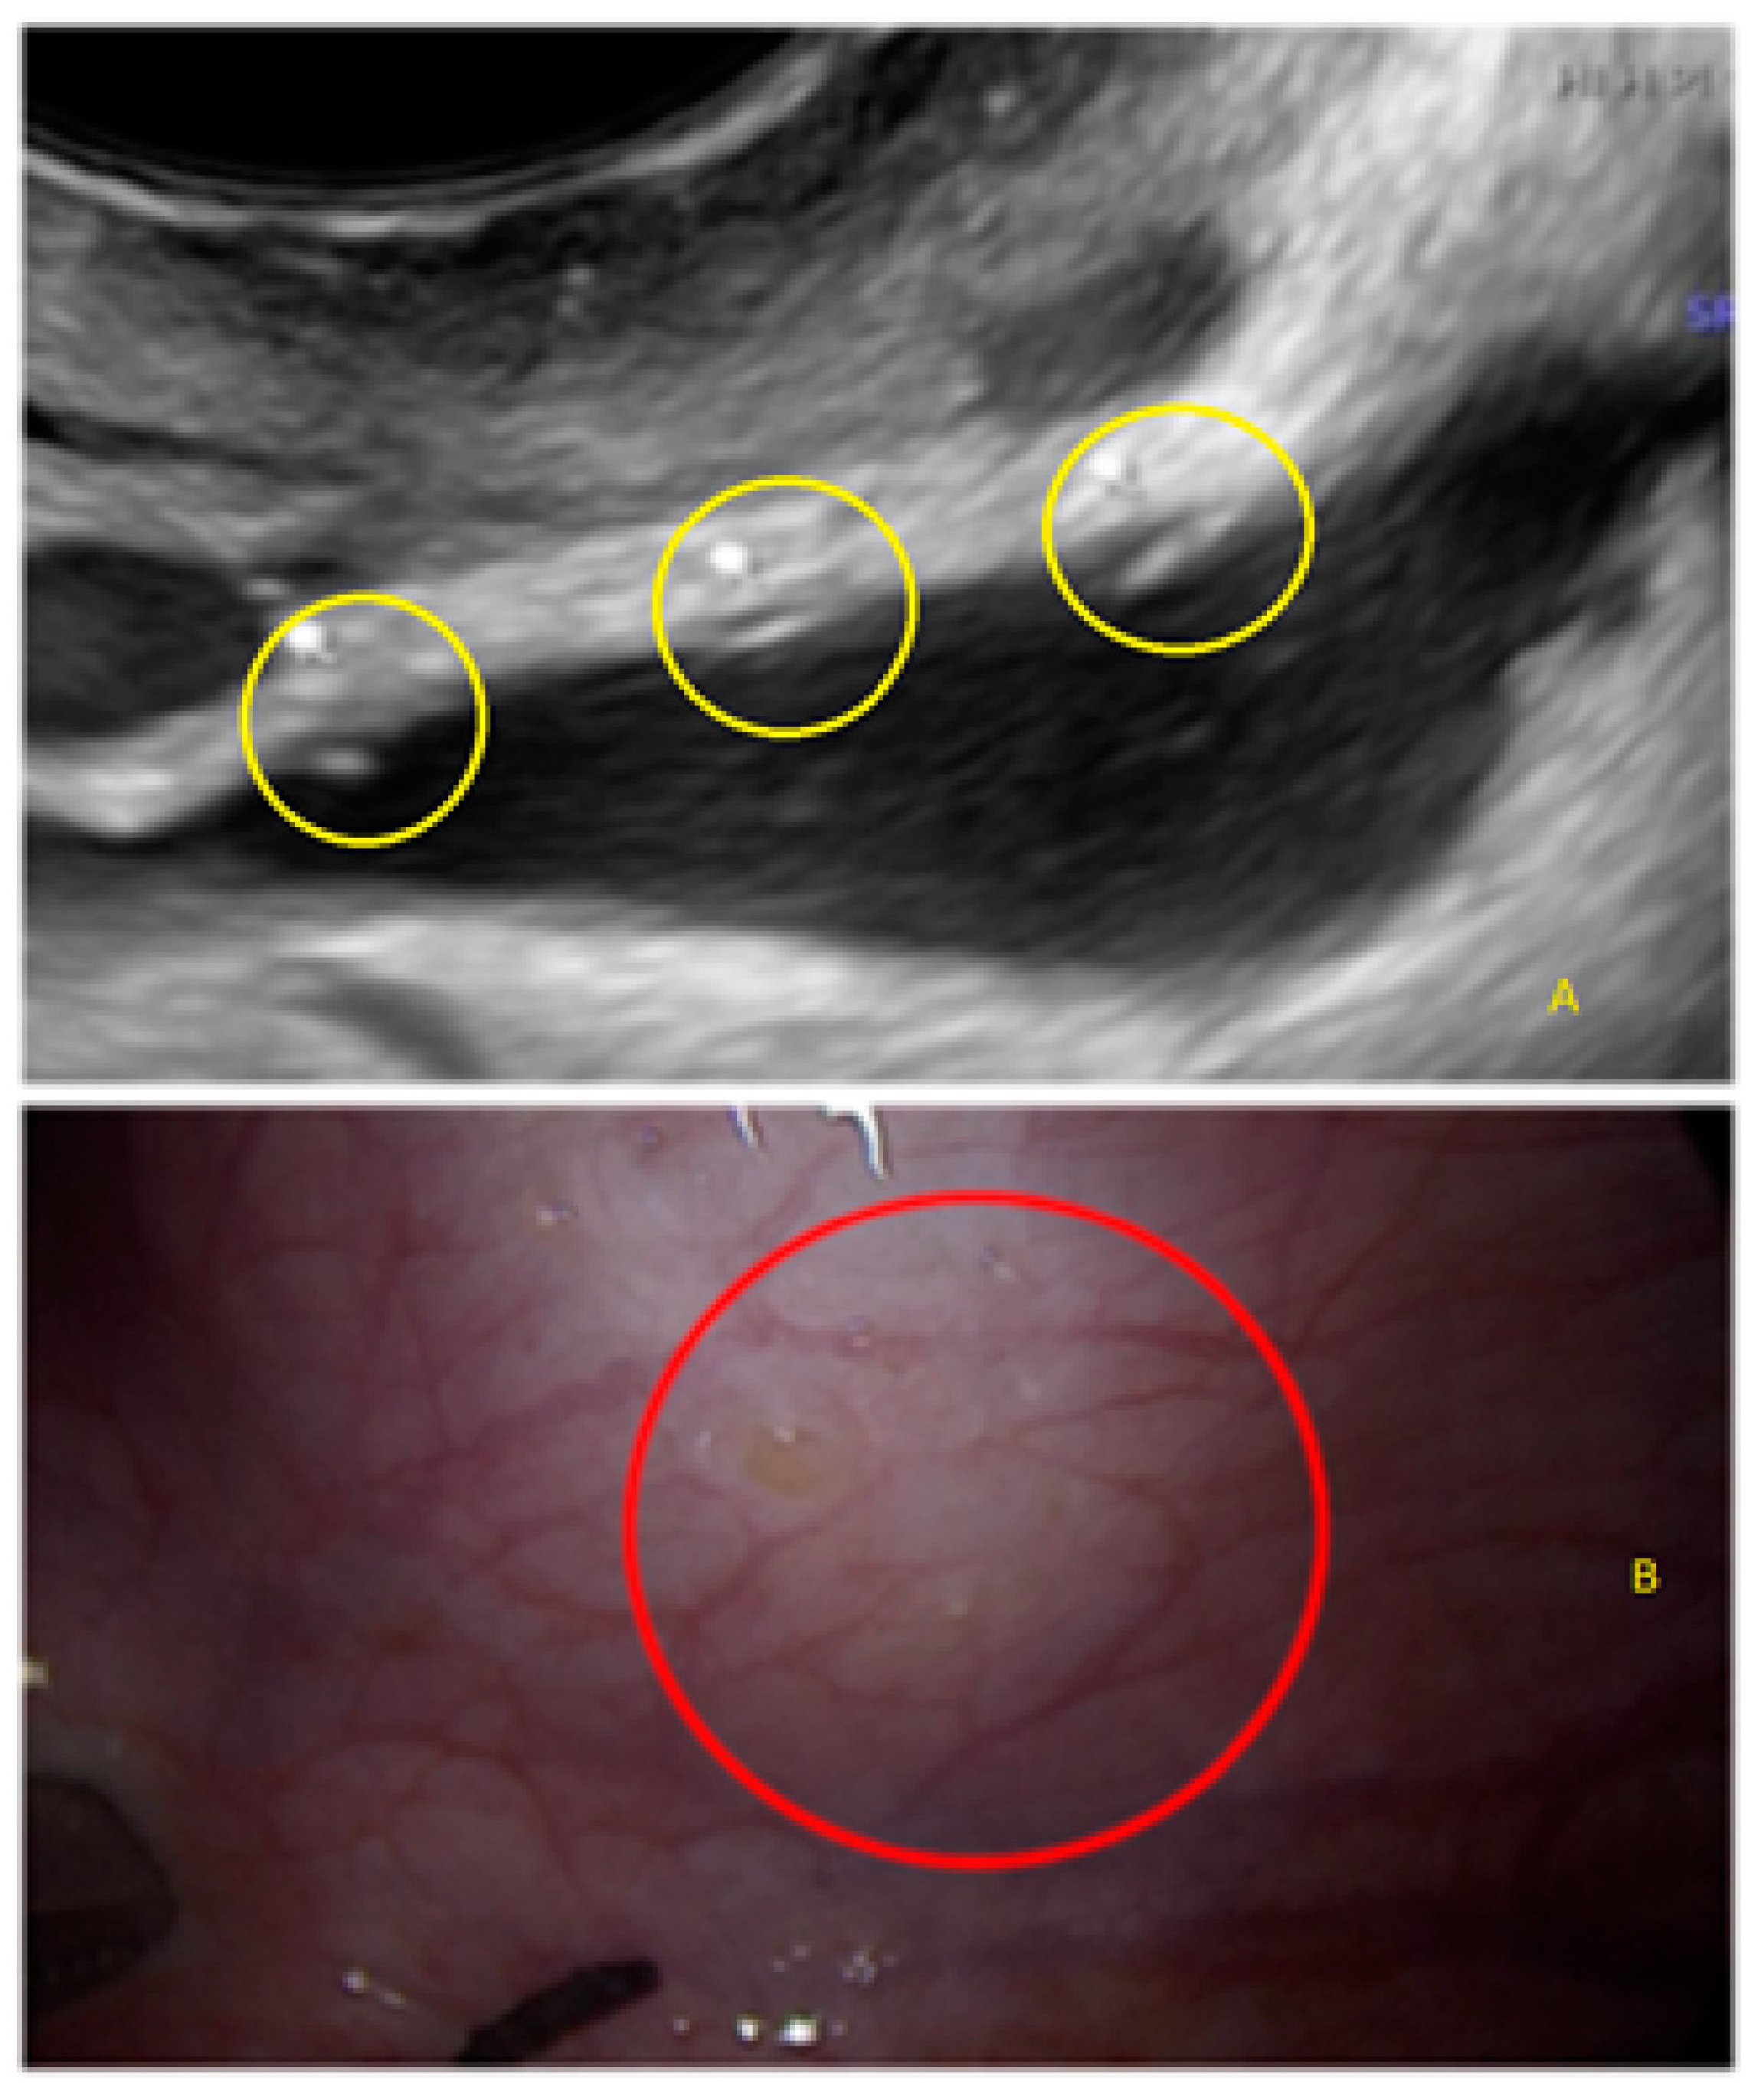

- The presence of hypoechogenic associated tissue (hypoechoic areas surrounding a small cyst area; we called this a “hat”). This tissue does not protrude or invaginate the peritoneal surface.

- The presence of hyperechoic foci (we called this a “pearl”).

3.2. Cystic Multiple Separate Lesions